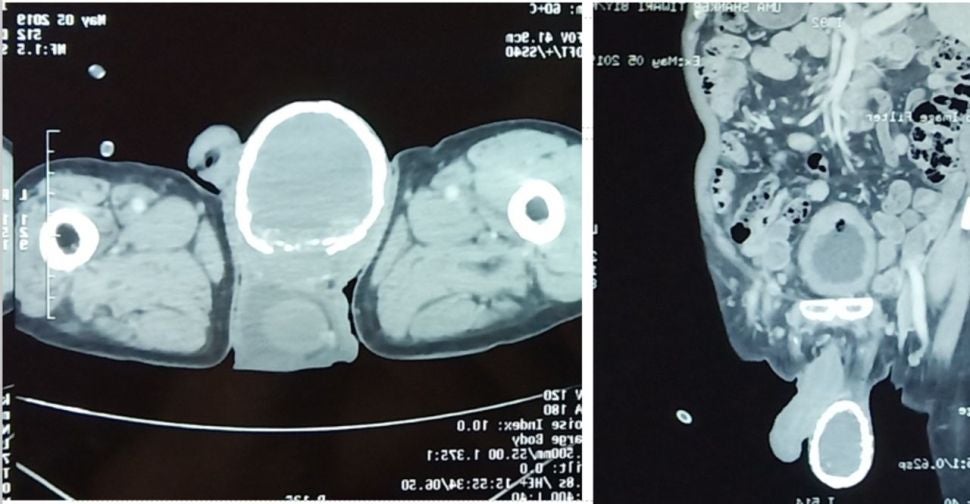

Once the man was examined via CT scan, doctors saw a fluid-filled sac that wasn’t supposed to be there. The type of sac they discovered is called a hydrocele, which forms when fluid builds up in a thin lining that surrounds a testicle. It often shows up in newborns, disappearing by the time they turn one without causing any damage. But when it happens in older men, it’s usually because of a local injury or inflammation to the scrotum, the latter of which is often caused by an infection.

Lymphatic filariasis, as it’s known, is unfortunately endemic in India. And in endemic parts of the world, these infections are actually the most common cause of hydrocele in men, according to the case study authors. But the “eggshell calcification” of the man’s testicle is an extremely rare complication, likely the result of a very long infection within the sac, one that caused calcium to form around it.